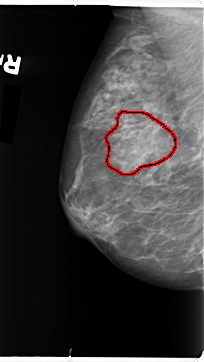

B_3101_1.RIGHT_MLO

RIGHT_MLO LINES 4696 PIXELS_PER_LINE 2640 BITS_PER_PIXEL 12 RESOLUTION 50 OVERLAY

FILE: B_3101_1.RIGHT_MLO.OVERLAY

TOTAL_ABNORMALITIES 1

ABNORMALITY 1

LESION_TYPE MASS SHAPE IRREGULAR-FOCAL_ASYMMETRIC_DENSITY MARGINS ILL_DEFINED

ASSESSMENT 3

SUBTLETY 2

PATHOLOGY BENIGN

TOTAL_OUTLINES 1

BOUNDARY